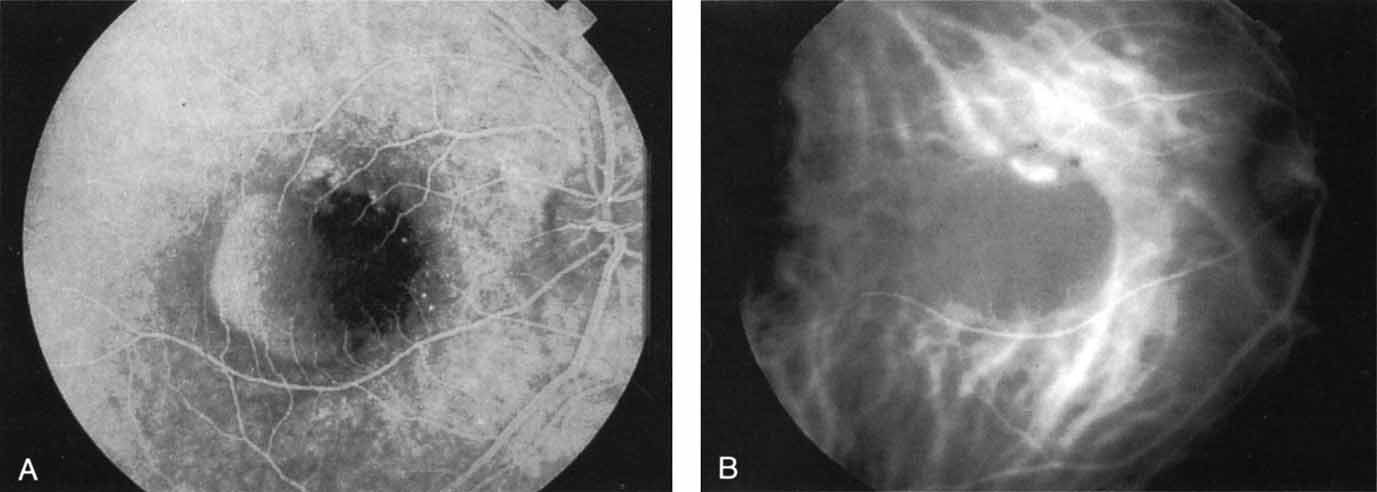

A number of choroidal tumors have been studied with ICG angiography.80,81 Pigmented choroidal melanomas block ICG fluorescence because of the absorption of the near-infrared light by the melanin-containing lesion. As a result, the choroidal and tumor vasculature cannot be visualized through the dense pigmentation. ICG has failed to provide distinguishing features that might help to differentiate a melanoma from other pigmented lesions, such as nevi or pigmented metastatic lesions; however, when a pigmented choroidal melanoma thickens or develops prominent intrinsic vasculature, ICG angiography reflects this change with an increase in fluorescence in the late phase.82

ICG angiography in amelanotic melanomas reveals variable blockage, depending on the amount of pigmentation present in the lesion. Corkscrew vessels have been identified with ICG angiography, but not with fluorescein angiography, in some patients with amelanotic melanoma80,81 (Fig. 24). The meaning of this vascular pattern currently is unclear, but it may eventually assist in the differentiation of these primary ocular tumors from metastatic lesions.

Fig. 24 A. Clinical photograph of a patient with an amelanotic melanoma adjacent to the optic nerve head. B. Mid-phase indocyanine green angiogram demonstrating corkscrew vessels within the melanoma.